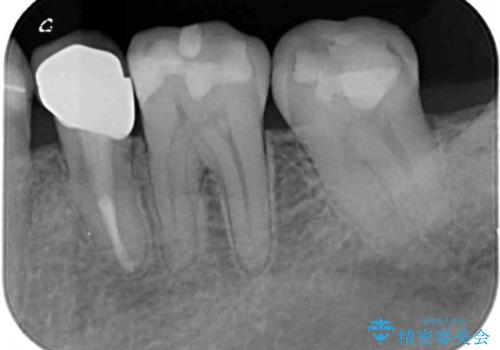

- 奥歯がしみるとのことで来院された患者様です。

診査をしたところ、目視でも明らかな、とても大きなむし歯があありました。

既に治療により詰め物が装着されている歯であったため、オールセラミッククラウンによる補綴治療を選択することとしました。